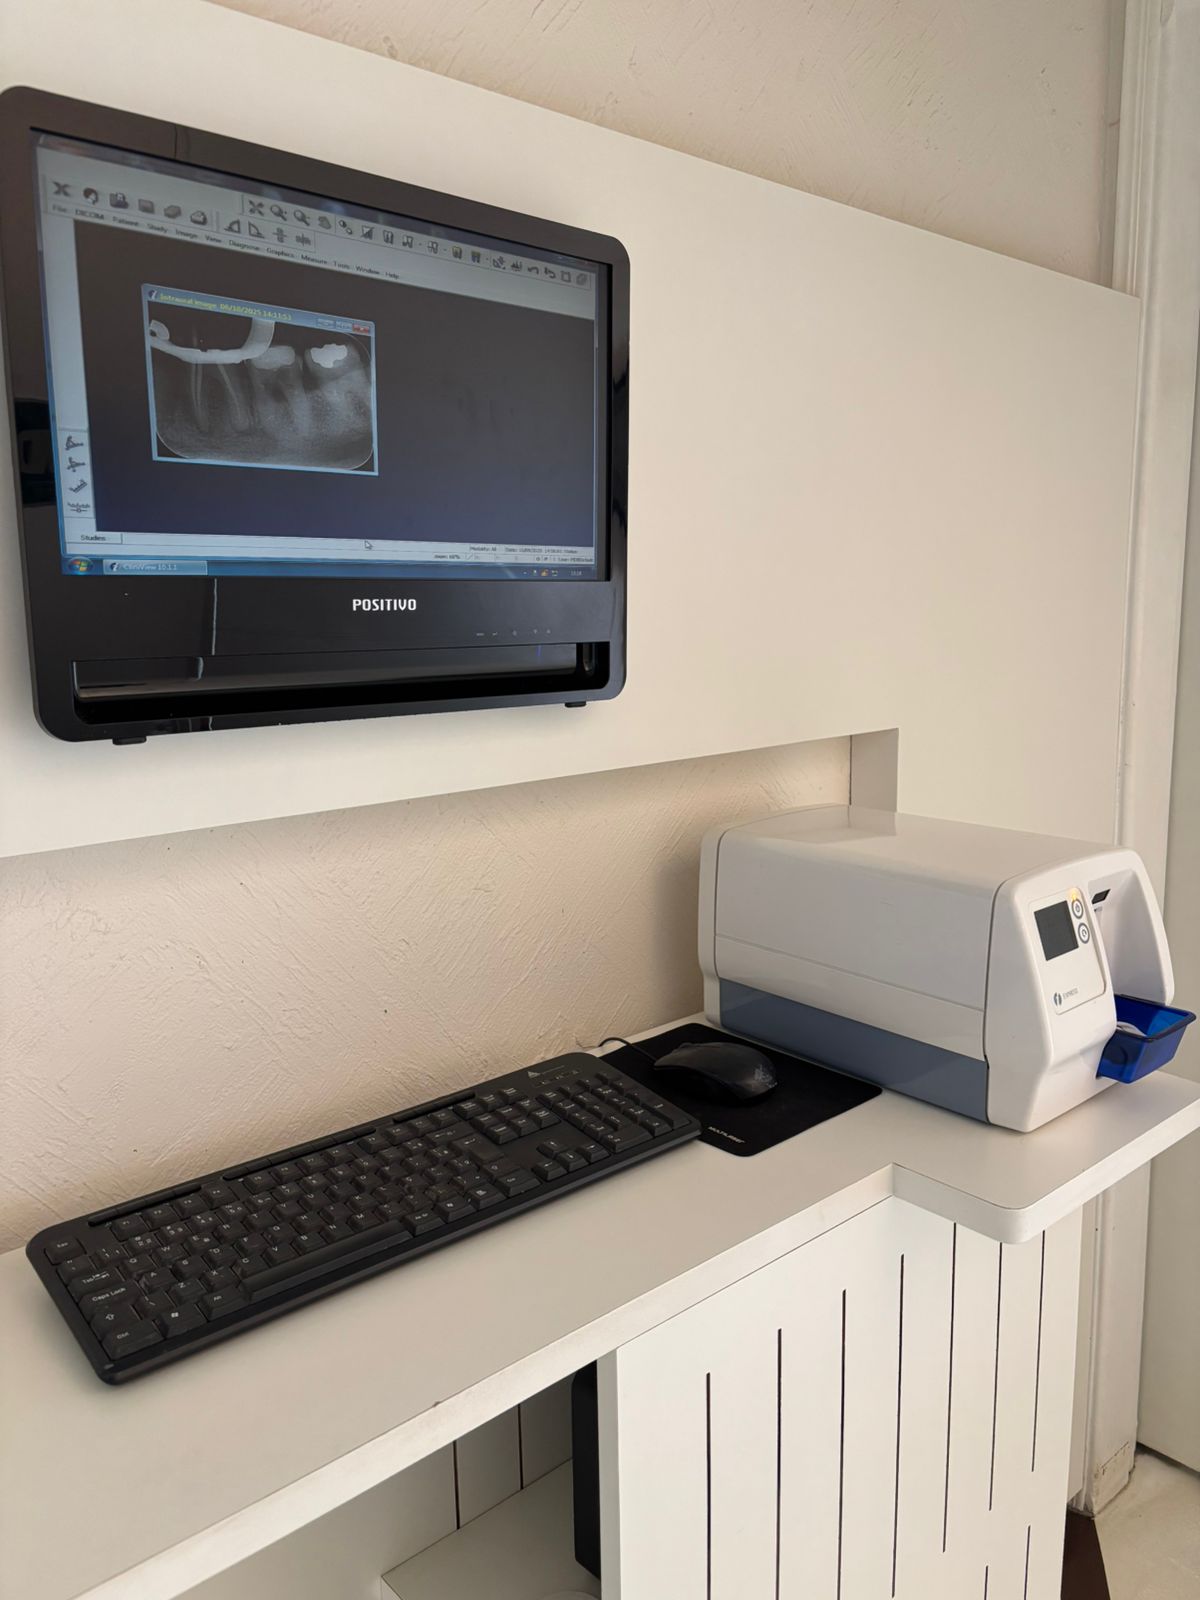

No COES, a tecnologia, conforto e resultados são parte essencial do cuidado. Nosso fluxo de trabalho, totalmente digital, integra a tecnologia CAD/CAM, Chairside, através do uso de Scanner Intraoral, Software de Planejamento, Impressora 3D, Fresadora e Tomografia de Alta Resolução.

Check-up Digital

Diagnóstico com Scanner Intraoral e Radiografias Digitais.